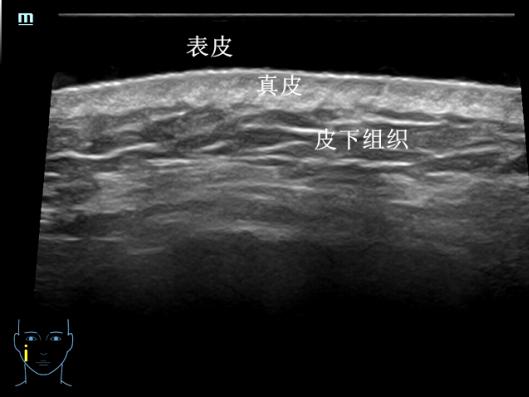

一、皮肤结构的精细呈现

我们的皮肤从外到内分为表皮、真皮、皮下组织三层,就像一层薄外套裹着两层“保暖层”。在超高频探头下,薄薄的皮肤可以变成一张 “皮肤剖面图” ,不仅可以看到表皮、真皮、皮下组织的结构,精确测量其厚度,还可以清晰显示其内的毛发、毛囊、皮脂腺等肉眼及普通超声无法识别的结构。